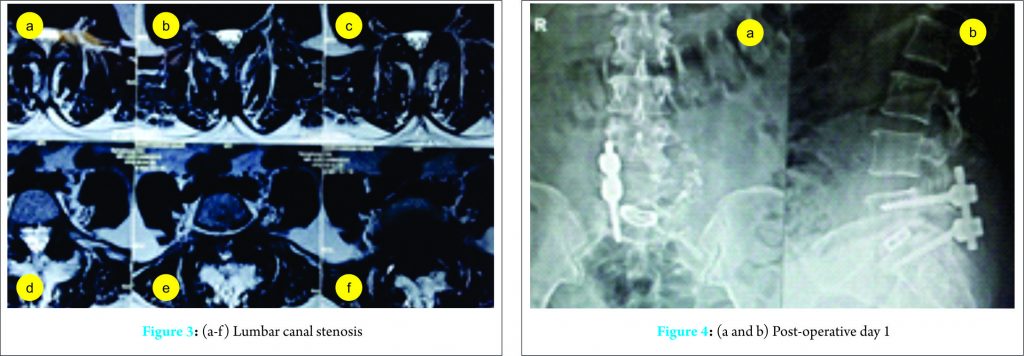

A 53-year-old female presented to our outpatient department with low back pain that had persisted for few years. The patient experienced severe left lower extremity pain for several weeks with no history of trauma. The pain limited her walk to <10 m in a stretch. She had no history of previous spinal surgery. The patient was treated at a local hospital with oral analgesics. However, intermittent claudication and pain persisted. The motor examination did not reveal any weakness; however, there was hypoesthesia in the S1 dermatome. Plain radiographs revealed degenerative Meyerding Grade I spondylolisthesis at L5-S1 (Fig. 1) [5]. Subsequent magnetic resonance imaging done revealed an associated prolapsed intervertebral disc and lumbar canal stenosis (Fig. 2 and 3).

She was given a trial of caudal epidural steroid injections for symptomatic relief. The patient did not improve, and hence, surgical intervention in the form of bilateral pedicle screw fixation with interbody cage was planned. The patient underwent posterior decompression through left-sided laminotomy followed by pedicle screw fixation on the right side. Screws were inserted in the pedicle of L5-S1. An optimal hold of the screw in the left pedicle of L5 could not be achieved due to the poor quality of bone; hence, intraoperatively, the plan was revised from bilateral to unilateral pedicle screw fixation. Further, a transforaminal interbody cage was inserted. Optimal placement of the implant and the reduction was confirmed intraoperatively under C-arm (Fig. 4).